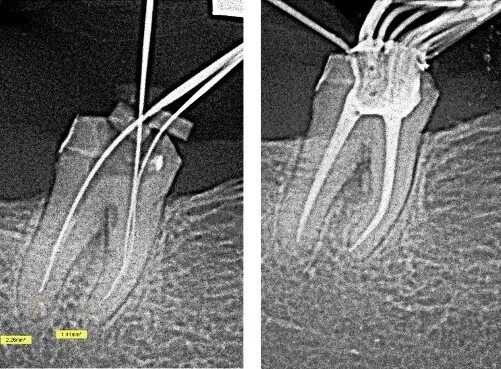

Удалить нервы запломбировать